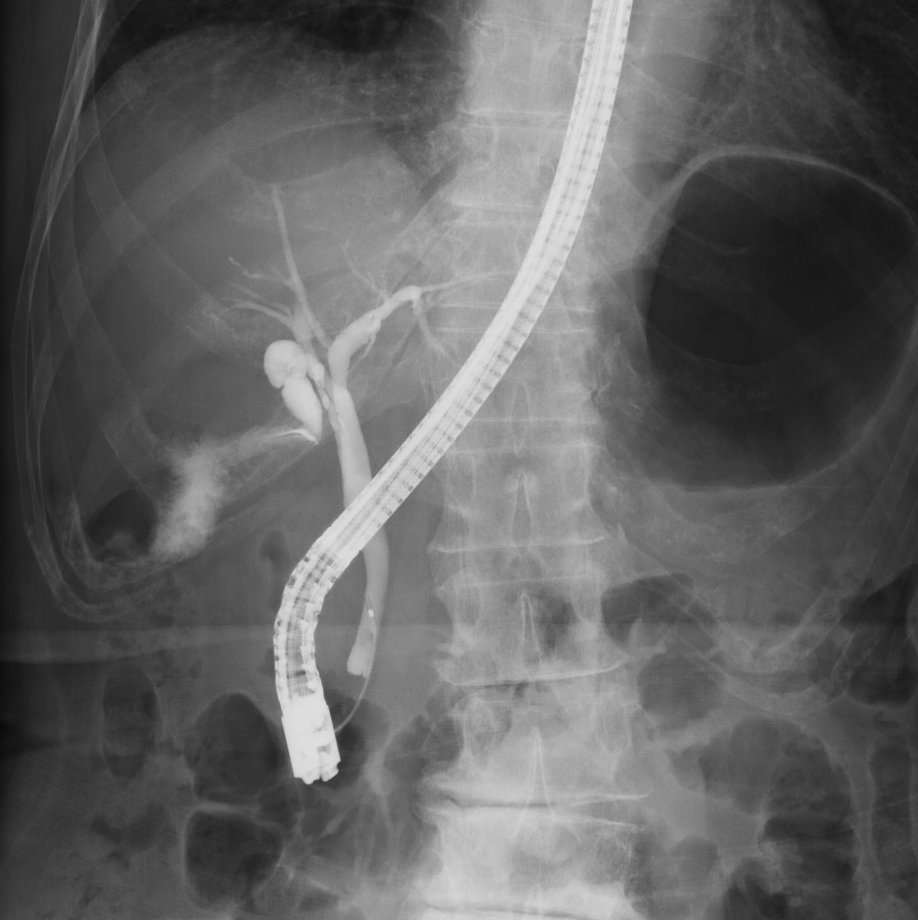

血管撮影装置

当院は令和6年3月の新病院発足に伴い、より高精度で安全な検査・血管内治療(IVR:Interventional Radiology)を提供するため最新の島津製作所製バイプレーンシステムTrinias B12s(Opera smart)を導入しました。

平面型X線検出器(FPD:Flat Panel Detector)を搭載し、カテーテルを用いた高度な血管内治療においてより少ないX線で高い解像度の画像を描出可能となりました。

バイプレーンシステムを採用したことにより、一回の造影剤注入で2方向撮影が可能となり、従来のシングルプレーンと比較して造影剤使用量を半分程度に抑えることができ、被ばくを低減すると共に検査時間の短縮にも繋がり、より患者さまの負担を軽減することが可能となりました。

冠動脈造影検査(CAG:Coronary Angiography)をはじめ、経皮的冠動脈インターベンション(PCI:Percutaneous Coronary Intervention)、下肢動脈のインターベンション(EVT:Endovascular Treatment)、肝動脈化学塞栓術(TACE:Transcatheter Arterial Chemo-Embolization)等、心血管領域、腹部血管領域における高度なカテーテル治療においてその性能を発揮しております。